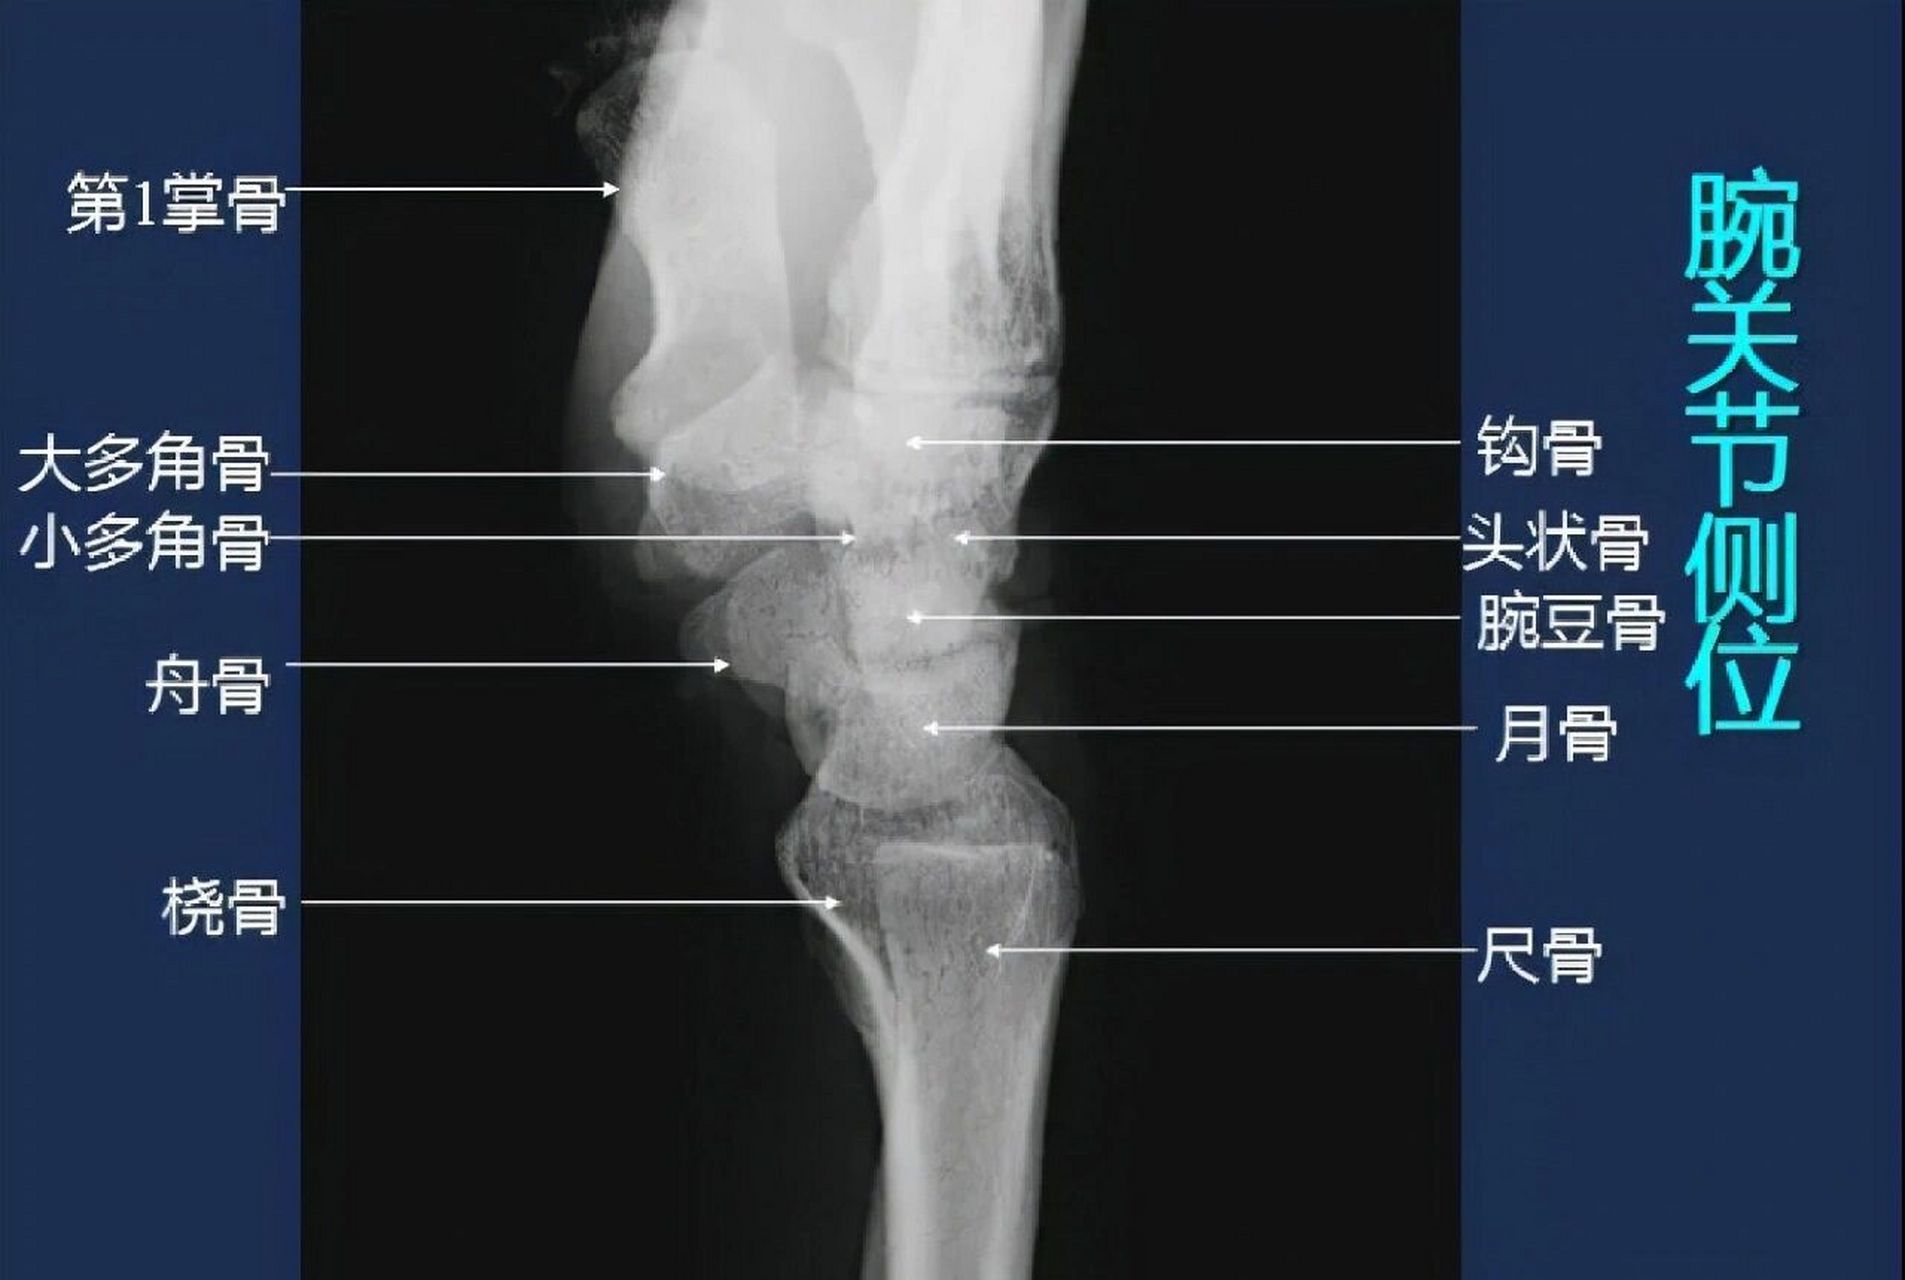

腕关节x线解剖图

图片尺寸1905x1280